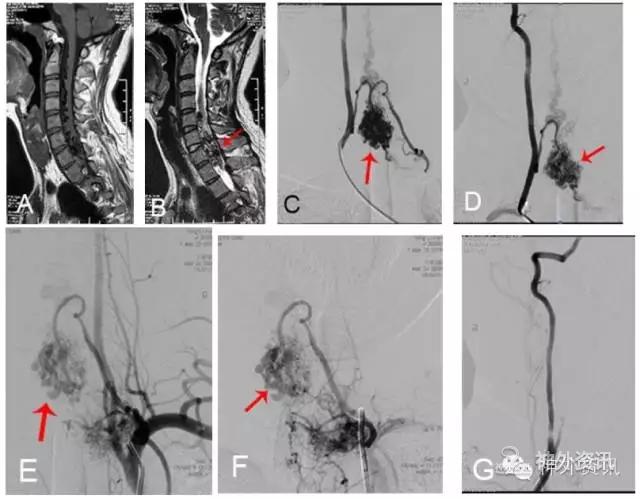

图7: 下颈段脊髓动静脉畸形(AVM)。A、B. MRI矢状位影像,↑示血管流空影;C、D. 2D-DSA,右椎动脉供血AVM,↑示畸形血管团;E、F. 2D-DSA,左曱状颈干供血AVM,↑示畸形血管团,经椎动脉与甲状颈干行血管内线段栓塞治疗;G. 栓塞后右椎动脉造影示AVM消失,术后四肢肌力五级,隨访至今无复发。